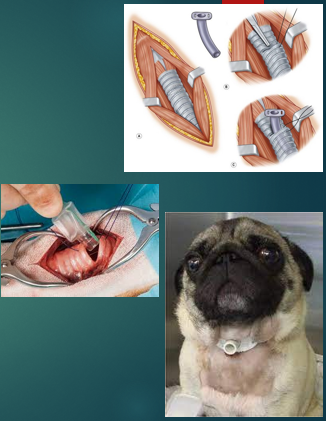

Management of URT obstruction - often emergency situations (time critical!)

Emergency tracheostomy

‘trach’ = trachea

‘-ostomy’ = make a hole in

Bypasses obstruction

Temporary relief whilst obstruction cleared

Done if an ET tube cannot be passed due to a foreign body or obstruction